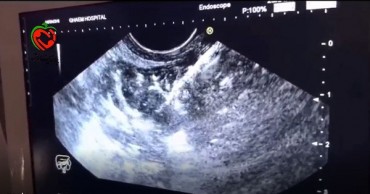

دکتر موسی الرضاحسینی با بیان اینکه این عمل تا کنون به روش جراحی باز انجام می شد خاطر نشان کرد: با تجهیز بیمارستان قائم(ع) به دستگاه مورد نیاز عمل گاستروژژنوستومی به طریق آندوسونوگرافی معده به قسمت ژژنوم روده آناستاموز ( چسبانده ) میشود تا راه خروجی معده به این وسیله برای بیمار باز شود.

عضو هیأت علمی دانشگاه علوم پزشکی مشهد با بیان اینکه از طریق دستگاه آندوسونوگرافی، استنت ها در محل قرار داده می شود تصریح کرد: در این روش نیازی به باز کردن شکم بیمار نیست و عمل جراحی به مدت ده دقیقه انجام شده و نیاز به بستری طولانی مدت بیمار نیست.